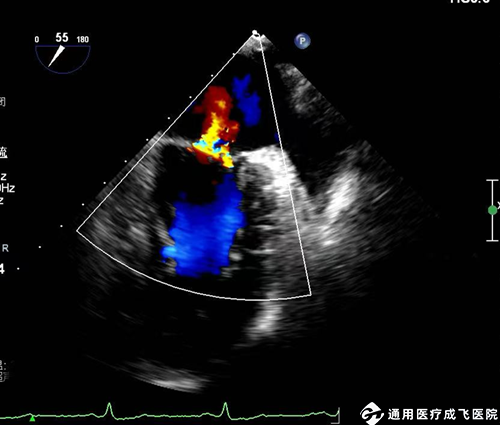

4.心脏瓣膜病:如瓣膜狭窄、关闭不全、脱垂等。

(经食管超声显示二尖瓣反流)

6.心脏瓣膜置换术后,TEE超声图像优于TTE,可对人工瓣膜功能结构及功能准确评价,如有无人工瓣膜的狭窄、卡瓣、瓣周漏、感染性病变、血栓、血管翳等并发症。